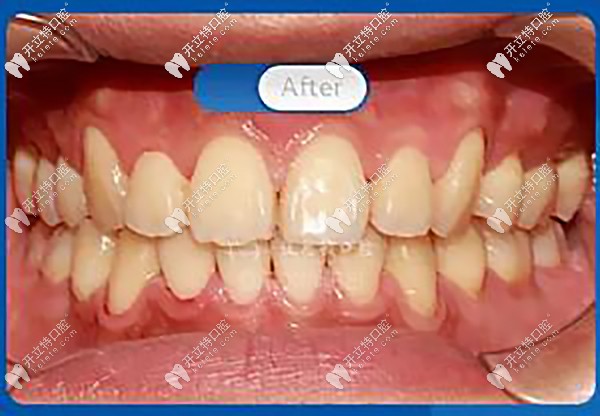

歷經(jīng)24個(gè)月終于完成了矯正,快看看我的變化吧!

正面看,內(nèi)收前牙,排齊牙列、牙中線,解除磨牙深覆蓋,恢復(fù)正常咬合關(guān)系。

笑容自信陽(yáng)光有感染力

花了兩年的時(shí)間,摘下牙套之后真的有種整牙如換頭的感覺,嘴凸改善了,好看的下頜線也出來(lái)了,重要的是,大家都說(shuō)我原來(lái)笑起來(lái)好看,現(xiàn)在的我再也不害怕微笑了。